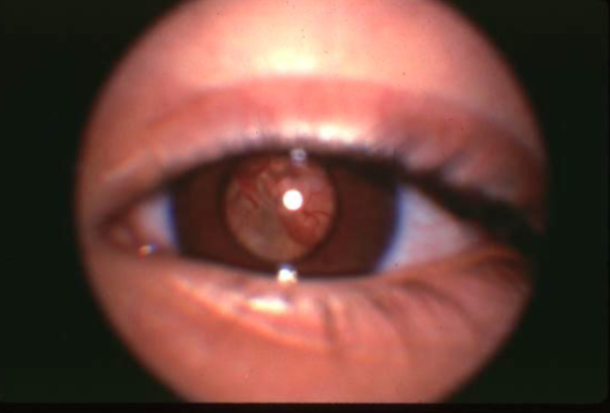

melanocytosis/uveal melanoma

melanocytosis/uveal melanoma